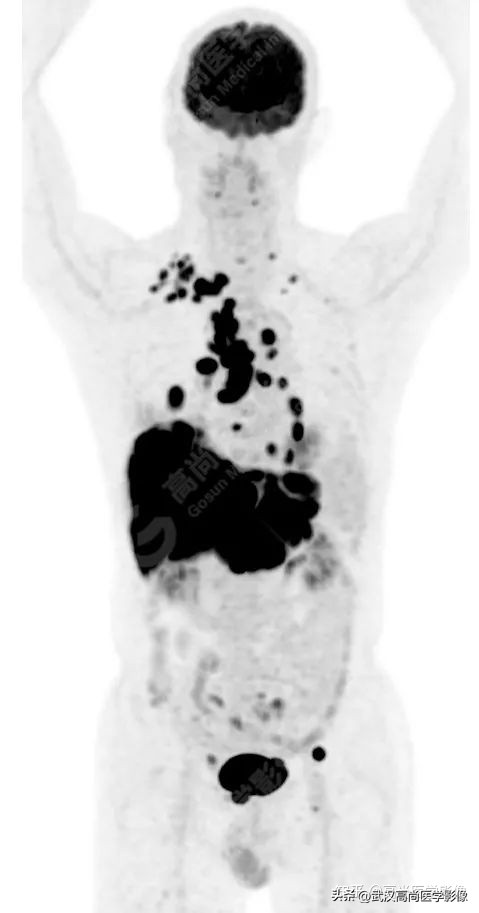

全身(右侧颈部、双侧锁骨上区、双侧腋窝、右侧胸小肌后间隙、右侧肺门、纵隔、胰腺周围)多发淋巴结肿大,最大约3.8cm×3.3cm,FDG高摄取,SUVmax6.6。

脾脏一低密度结节,FDG高摄取,SUVmax为3.6。

左侧第2、7肋骨质破坏,合并病理性骨折。

右肺上叶后段一实性结节,大小约1.4cm×1.0cm×1.2cm,边缘分叶征、棘状突起,邻近胸膜稍牵拉,FDG高摄取,SUVmax6.6。

右肺上叶后段周围型肺癌,伴淋巴结、脑、脾脏、肋骨多发转移。